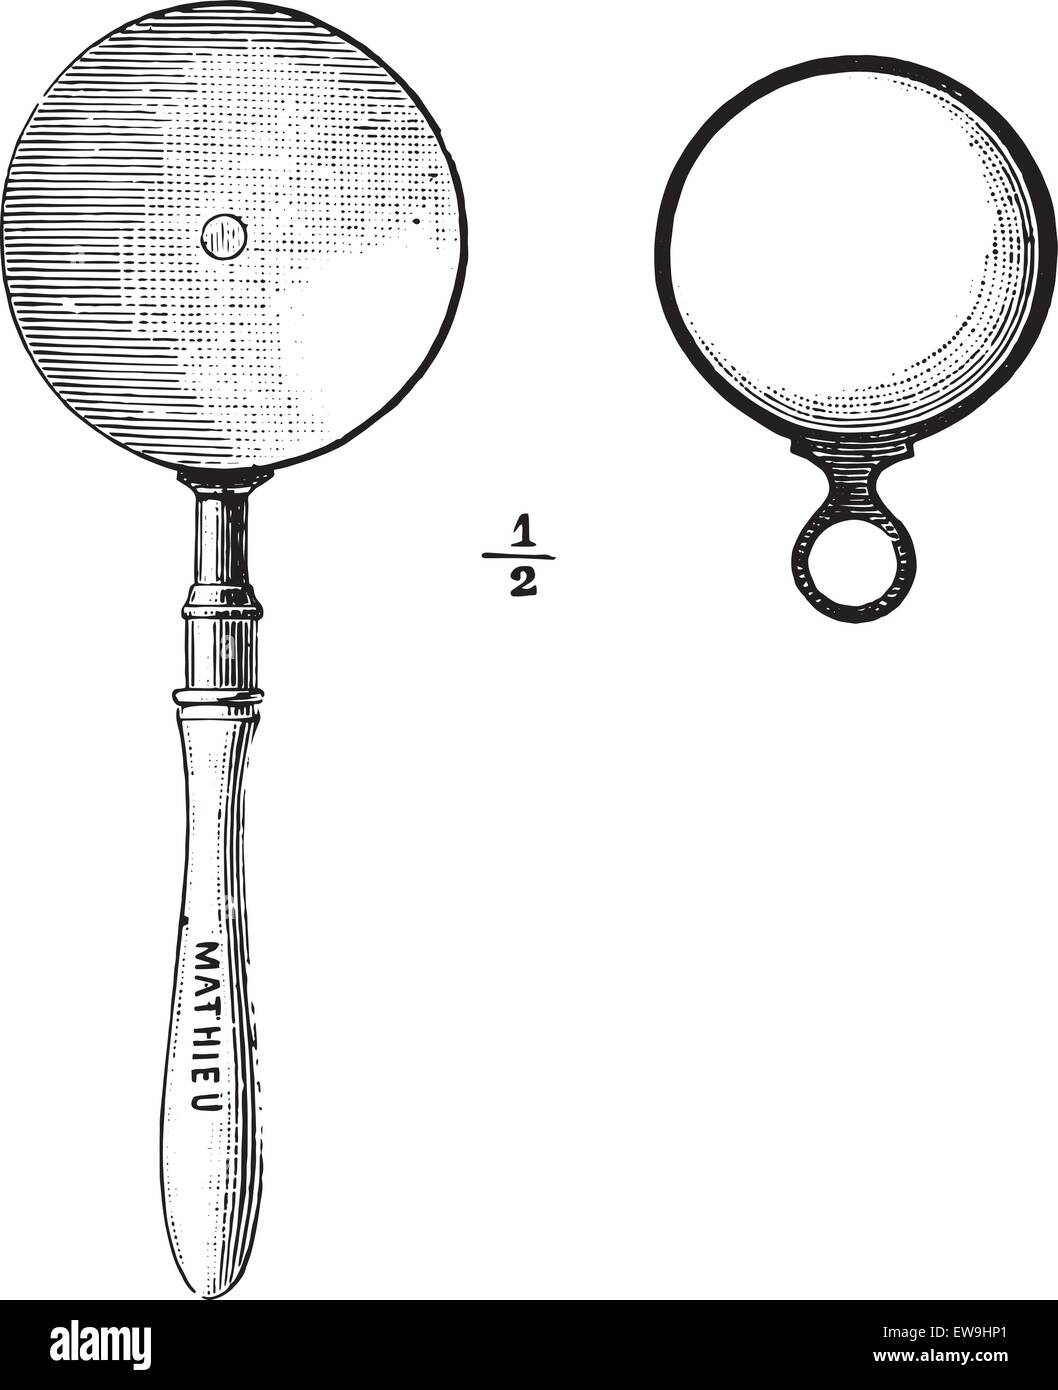

Ophthalmoscope, vintage engraved illustration. Usual Medicine Dictionary - Paul Labarthe - 1885. Stock Vectorhttps://www.alamy.com/image-license-details/?v=1https://www.alamy.com/stock-photo-ophthalmoscope-vintage-engraved-illustration-usual-medicine-dictionary-84419385.html

Ophthalmoscope, vintage engraved illustration. Usual Medicine Dictionary - Paul Labarthe - 1885. Stock Vectorhttps://www.alamy.com/image-license-details/?v=1https://www.alamy.com/stock-photo-ophthalmoscope-vintage-engraved-illustration-usual-medicine-dictionary-84419385.htmlRFEW9HP1–Ophthalmoscope, vintage engraved illustration. Usual Medicine Dictionary - Paul Labarthe - 1885.